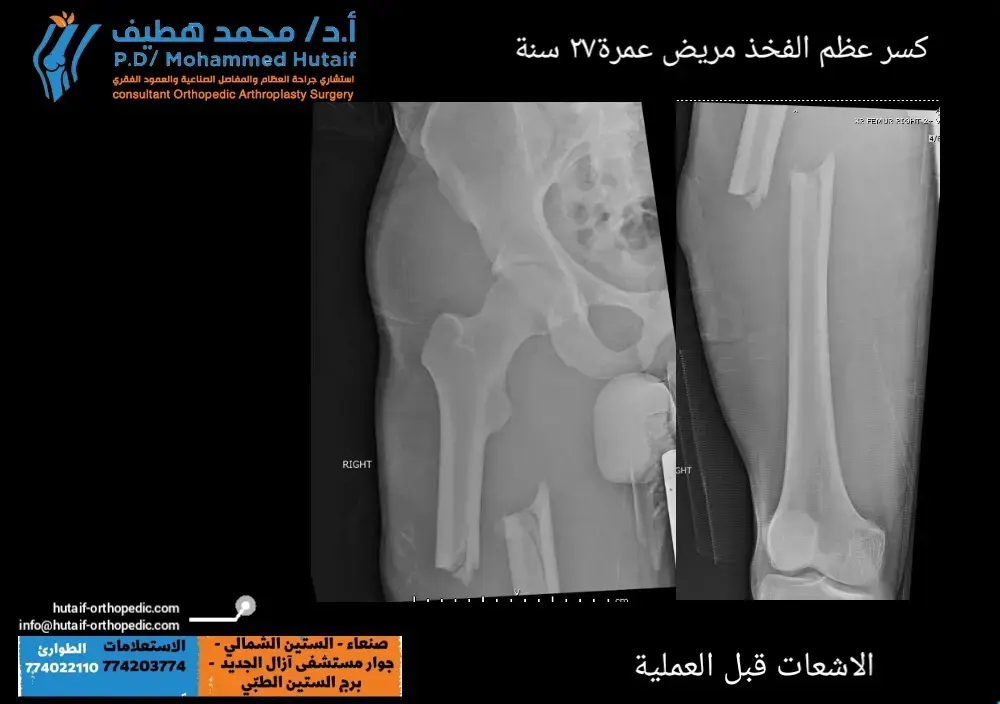

الكسور حول المفصل الاصطناعي (Periprosthetic Fractures):

كسور تحدث في العظم المحيط بالمفصل الاصطناعي، وقد تتطلب ترميمًا معقدًا.